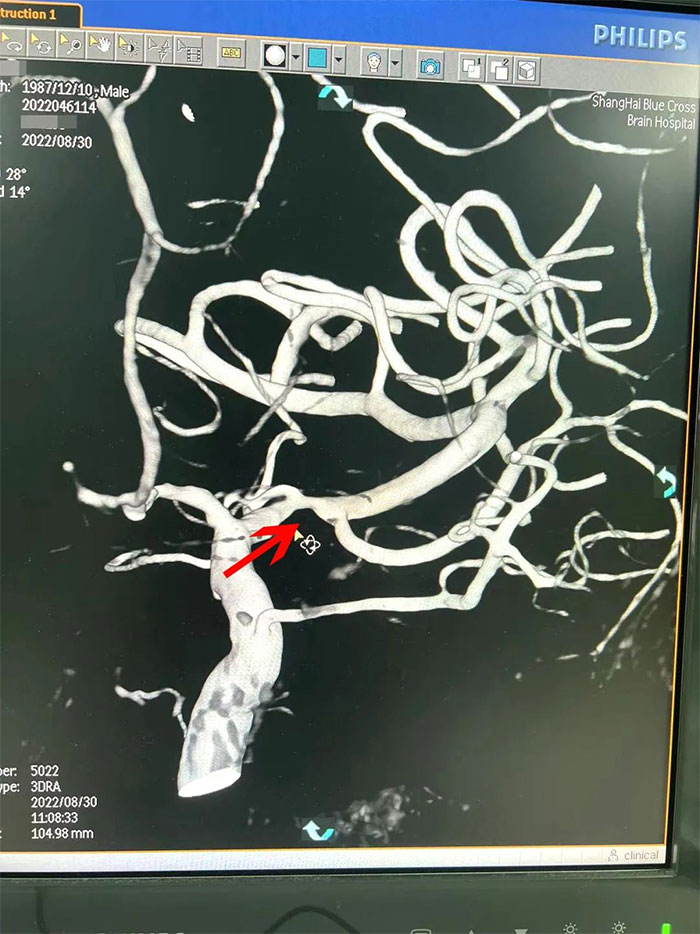

在與患者及家屬充分溝通后,李振并主任為周先生展開了DSA(數(shù)字減影血管造影)檢查。

在檢查中發(fā)現(xiàn),周先生右側(cè)大腦中動脈M1段閉塞,可見煙霧狀異常血管網(wǎng)生成;左側(cè)大腦中動脈M1段重度狹窄(約70%)。符合煙霧病的典型影像學(xué)特征。

▲右側(cè)大腦中動脈M1段閉塞,左側(cè)重度狹窄

煙霧病又名Moyamoya病,腦底異常血管網(wǎng),是一組以Willis環(huán)雙側(cè)主要分支血管(頸內(nèi)動脈虹吸段及大腦前、中動脈,有時也包括大腦后動脈)起始部慢性進行性狹窄或閉塞,繼發(fā)出現(xiàn)側(cè)支異常的小血管網(wǎng)為特點的腦血管病。因腦血管造影時,呈現(xiàn)許多密集成堆的小血管影,似吸煙時吐出的煙霧而得名。